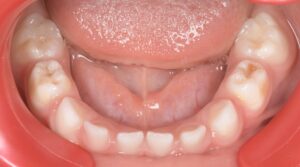

Le congrès de l’EAPD (Académie Européenne d’Odontologie Pédiatrique) a défini des critères de diagnostic en 2003. A savoir des opacités délimités, des fractures post-éruptives, des restaurations atypiques ainsi que que des extractions des molaires. (3) Le diagnostic différentiel doit surtout s’établir entre des amélogénèses imparfaites et des hypominéralisations d’origine traumatique pour les dents antérieures. Cliniquement, les dents vont présenter des colorations blanches ou brunes opaques sur une partie ou sur toute la surface de la dent (Figures 1-2-3-4).

formation dentaire pédodontie Figure 1.

MIH, état des lieux et thérapeutiques Figure 2.

Figures 1-2 : Incisives centrales atteintes de MIH

Figure 3-4 : Molaires atteintes de MIH (HSPM + MIH pour la figure 3)